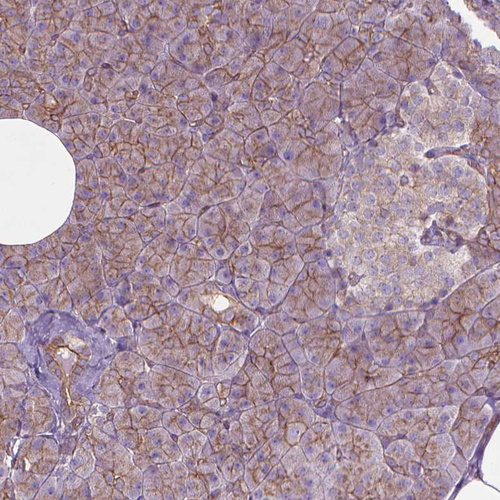

Immunohistochemical staining of human colon shows strong membranous positivity in glandular cells.